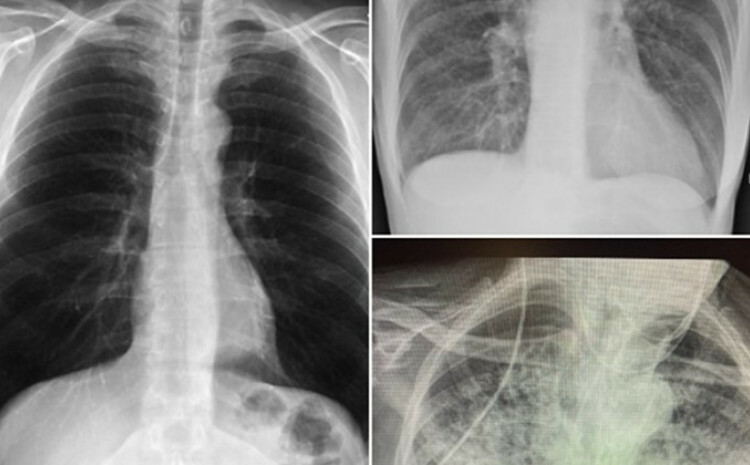

• 3 347

Usporedila pluća pušača i pacijenta koji je prebolio koronu: Ovo je užas

16.01.

Doktorica iz Teksasa Britani Bekhed Kendl (Brittany Bankhead-Kendall), koja je od prošle godine liječila hiljade bolesnika zaraženih koronavirusom, otkrila je…